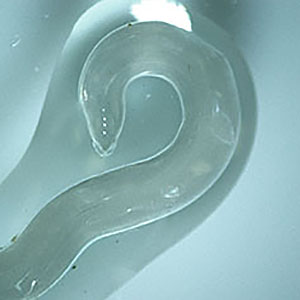

The object shown in Figures A–C was found in a stool specimen collected in SAF (sodium acetate-acetic acid- formalin) from a 43-year-old woman born and raised in Manitoba, Canada with no recent travel reported. Estimated length of the object was 8 millimeters. What is your diagnosis? Based on what criteria?

Figure A

Figure B

Figure C